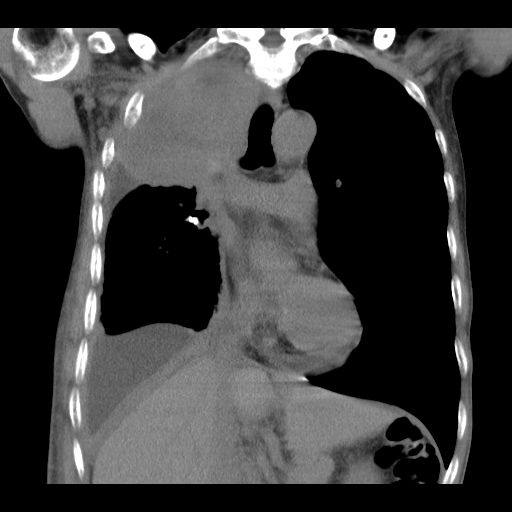

2020年5月12日,何叔来到复大就诊,检查结果:入院查CT示右肺中央型肺癌并右肺上叶及中叶阻塞性肺不张表现,肺腺癌T3bN2M1 Ⅳ期,伴胸膜、纵膈、右肺门等多发淋巴结转移,左侧胸腔中大量积液,右侧胸腔少量包裹性积液。针对何叔的病情,复大专家团队立马组织会诊,先后给予何叔静滴安维汀和两次动脉DSA+灌注化疗联合PD-1治疗,何叔的呼吸症状得到改善,肿瘤也从8.6公分缩小到4公分。

治疗后